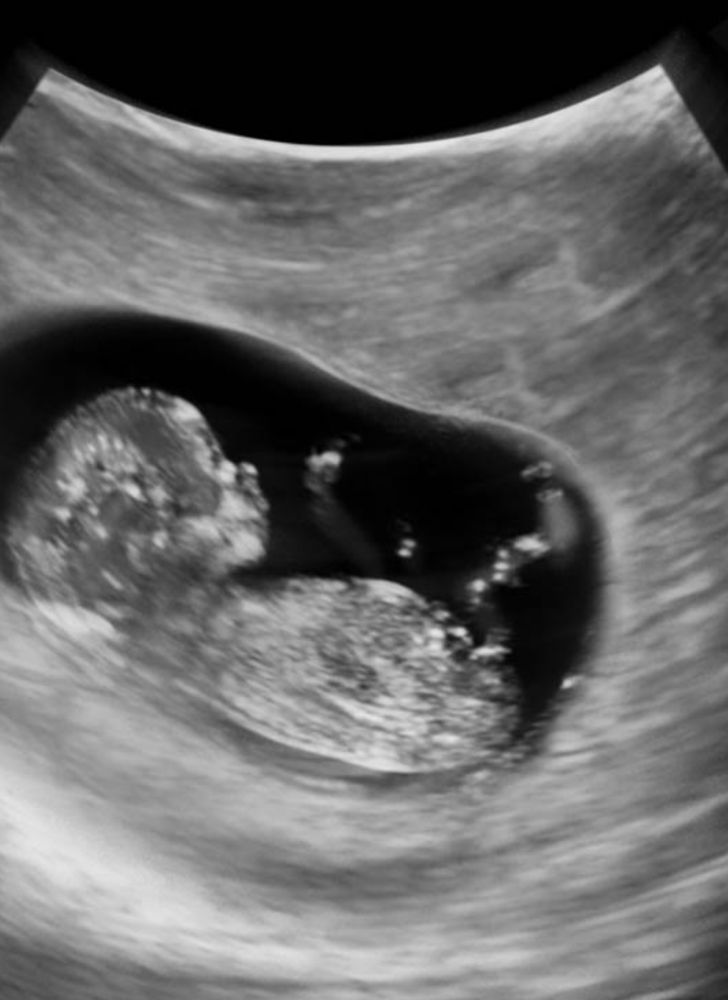

12 недель - первый скрининг пройден

Всё о нашей беременностиНам сегодня ровно 12 недель) кровь сдали) на узи были. Врач сказала «хорошая у вас лялька, лежит тихонько, пальчик сосет и показывает нам всё»🥰❤️ Каждый день болтаем с пузиком, ждём 3 недели чтобы узнать пол🙏🏼 Благодарю Бога за это счастье! ПДР ставят на 30.08😍